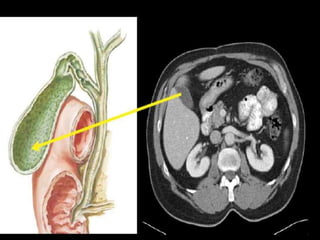

CT cross sectional anatomy.

CT – computedtomography. •Cross-sectional modality with capabilities for multiplanar reconstruction and dynamic imaging to assess vascularity •Tube rotates around the body and a circle of stationary detectors detects the penetrating x-rays forming an image.